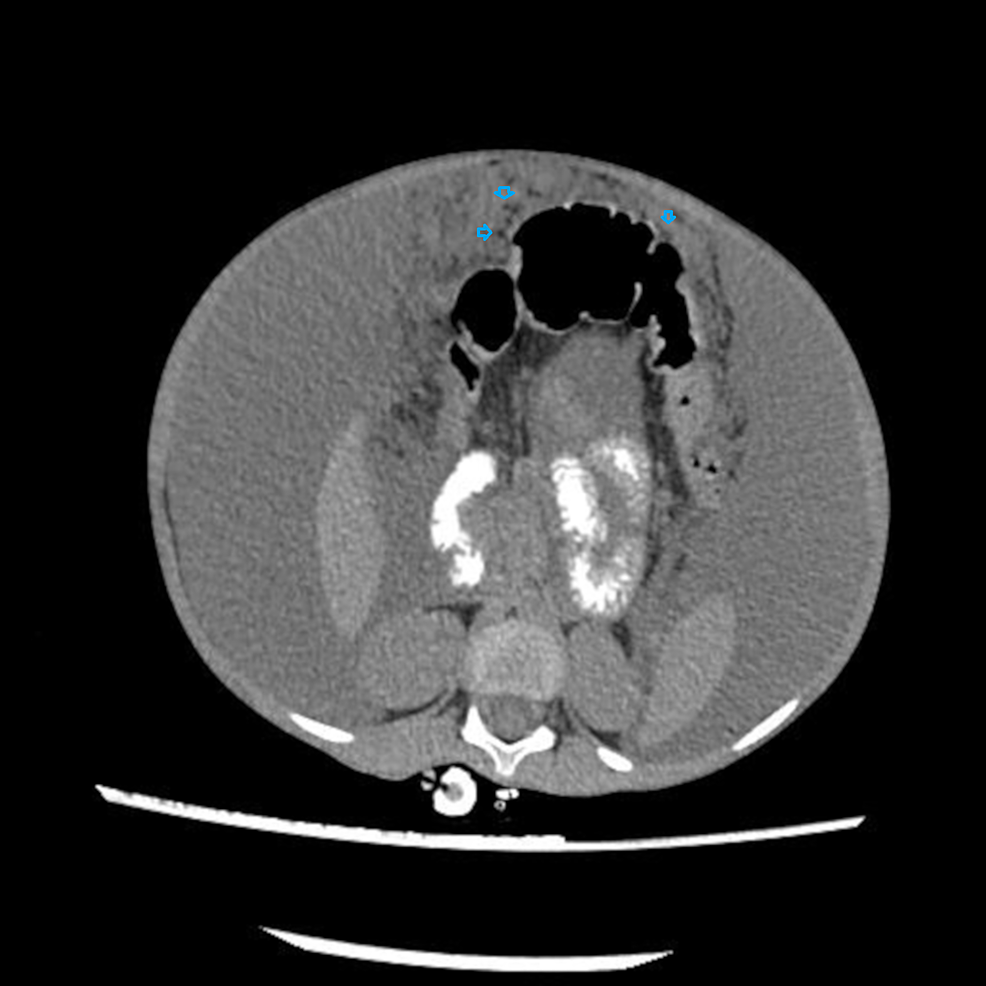

Ultimately CT abdomen showed gross ascites with omental thickening and nodularity (Figures 1-2). A laproscopic omental biopsy was performed. Grossly omentum and gut loops appeared normal. However, omental biopsy showed atypical lymphoid infiltrate (Figure 3). Immunohistochemistry showed lymphocytes positive for CD20 and Tdt while CD10 negative (Figures 4-5). In correspondence with these results precursor B-cell lymphoblastic lymphoma was diagnosed. After discussing the biopsy report with the child’s parents CHOP therapy has been initiated.